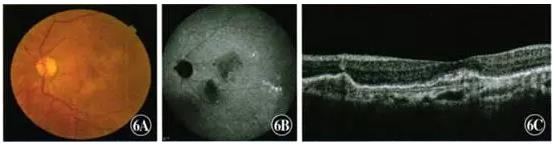

给予左眼玻璃体腔注射l0 mg/ml康柏西普0.05ml,每月1次,连续2个月,及1次玻璃体腔注射雷珠单抗。治疗后息肉状病灶未消退,再给予左眼PDT治疗1次,继续玻璃体腔注射雷珠单抗治疗2次。2015年12月15日复诊,视力右眼1.0,左眼0.6;左眼黄斑部鼻下方橘红色病灶消退,出血吸收。ICGA检查可见左眼黄斑部鼻下方息肉状病灶消退,出血吸收。OCT检查可见左眼黄斑区鼻下方PED明显减轻(图6)。

图6 左眼再复发时眼底检查 A:彩色眼底照相可见黄斑区鼻下方橘红色病灶消失,出血吸收 B:ICGA可见息肉状病灶消退,出血吸收 C:OCT检查可见黄斑区中心凹鼻下方RPE隆起明显减轻